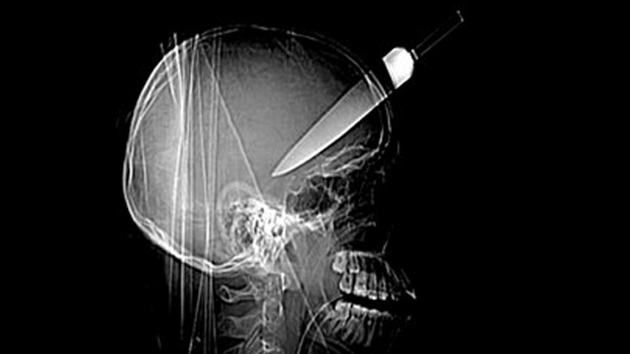

Una mujer china que sufre una enfermedad mental, de nombre Zhang Lan, se apuñaló a sí misma en la cabeza con un cuchillo en un descuido de sus cuidadores, y sin embargo sobrevivió milagrosamente y sin daños físicos serios.

En el hospital local los médicos se negaron a ingresarla como paciente por temor a que su intervención la dañara más aún, por lo cual fue trasladada tres horas después al hospital de Lanzhou en la capital de la provincia china de Gansu, donde sí fue aceptada.

Cinco días después, fue dada de alta luego de una exitosa operación que además no produjo efectos colaterales reportados.